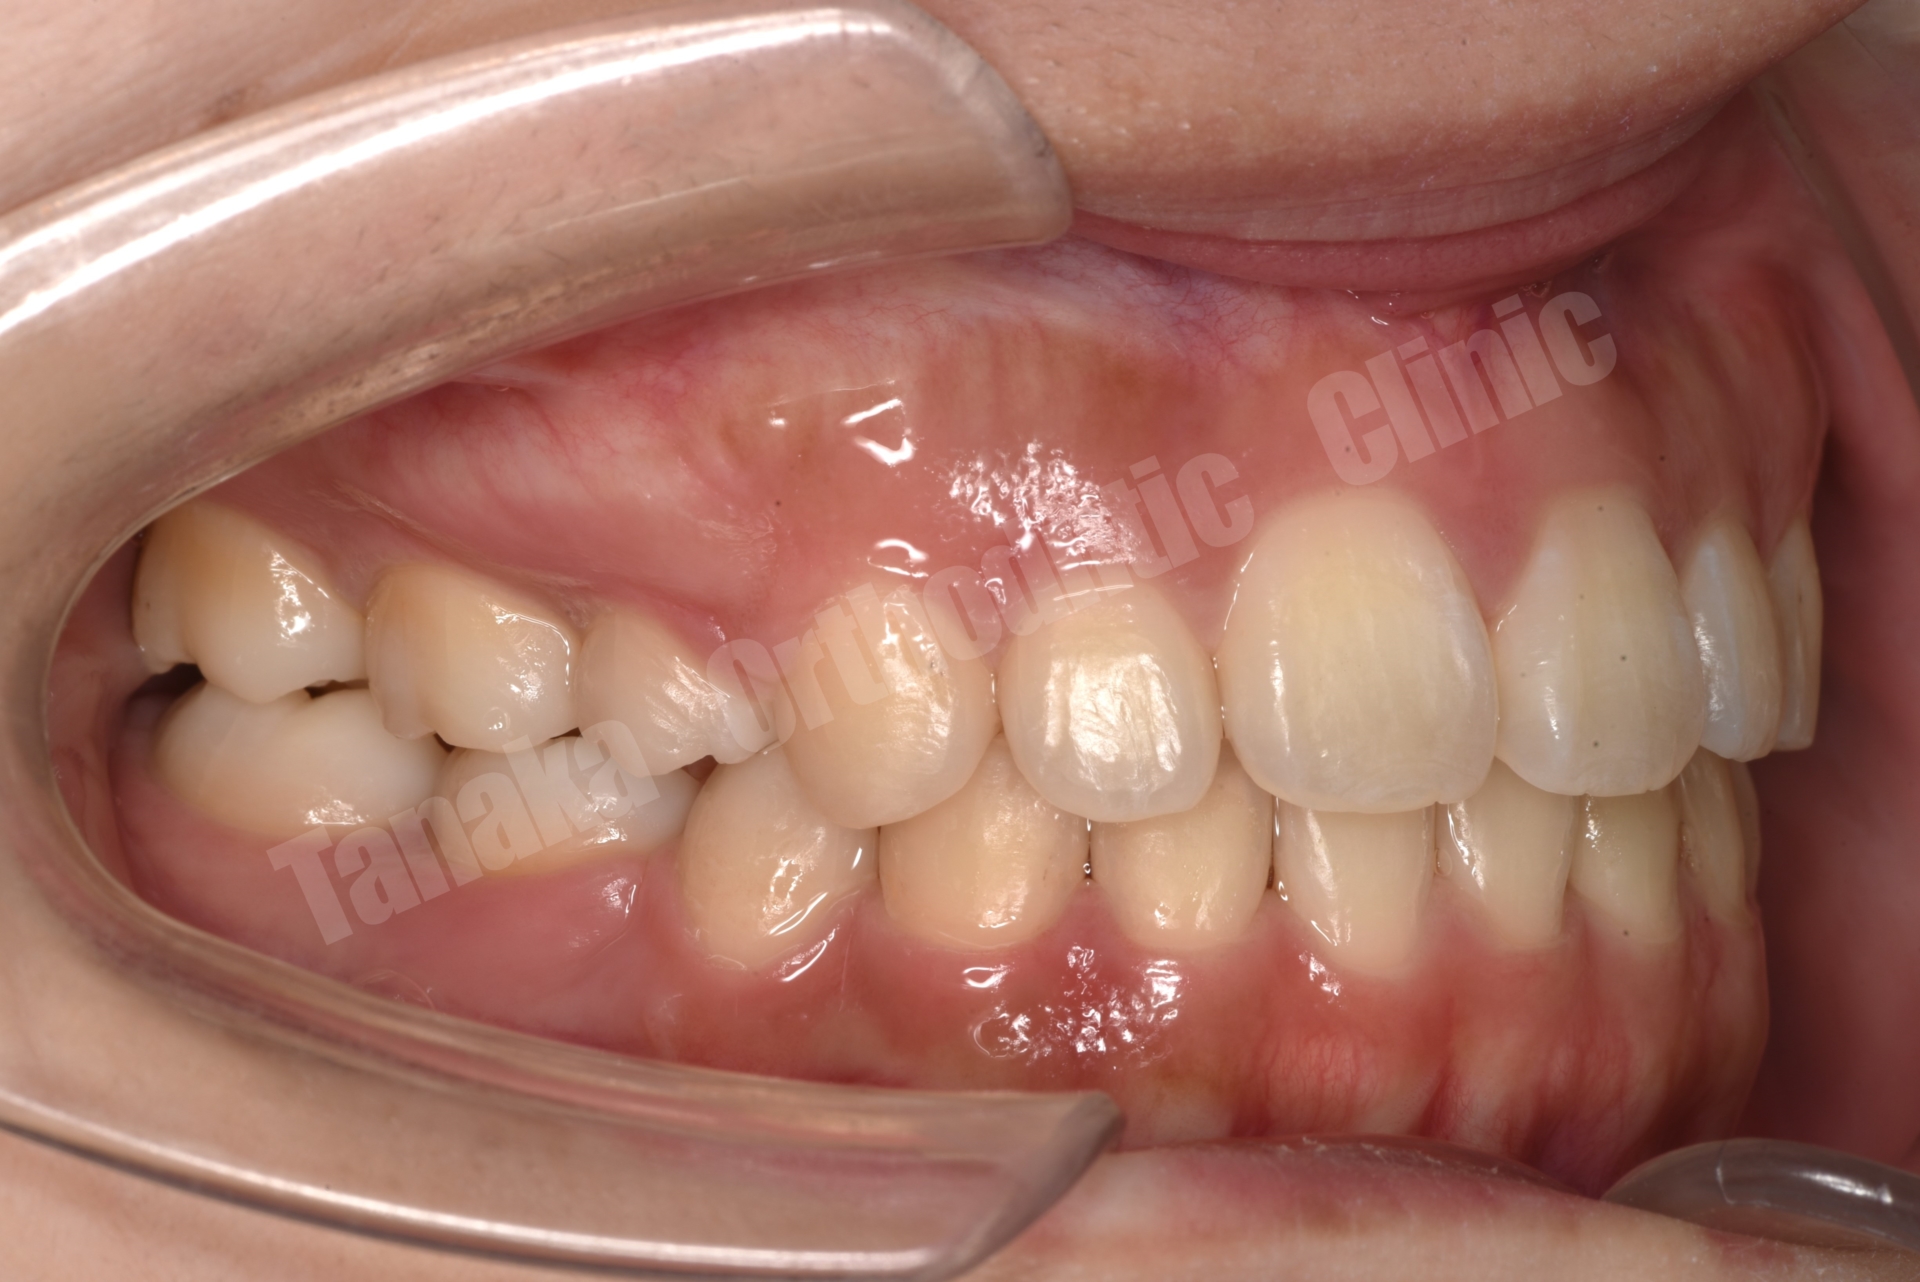

| 診断 | 上顎前歯の唇側傾斜(前歯部水平被蓋が大きい)、下顎正中の左偏位、右下E残存(5番の先欠)、下顎両側7番の位置異常(右側未萌出&左側半萌出)、上顎両側1番の歯根が短い |

初診時の診査では、上顎前歯が唇側に傾斜しており、前歯の水平被蓋(オーバージェット)が大きい状態でした。そのため口元の突出感が認められ、前歯部は十分に噛んでいない状態でした。また下顎正中は左側へ偏位しており、右下E(乳臼歯)の残存と5番の先天欠如、さらに下顎両側7番の位置異常も確認されました。さらに患者様は10代半ばの頃に一度、非抜歯でマルチブラケット矯正を受けており、その影響もあって上顎中切歯には歯根吸収が生じ、歯根がやや短くなっている所見も認められました。